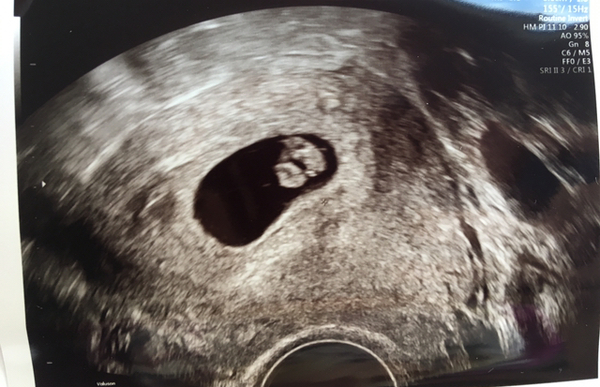

Whatelsecouldibecalled · 27/01/2020 18:38

Probably will be done transvaginally at that stage. Mine was. Here is my scan pic at 7+2. The blob on the left is baby. Blob on right is sac. We also saw heartbeat fluttering away. Was incredible after our first round of ivf